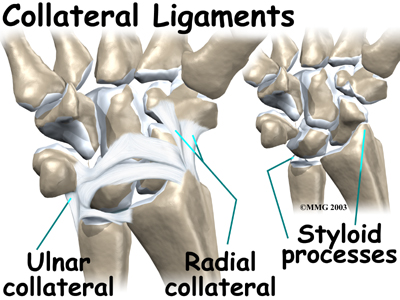

Two important ligaments support the sides of the wrist. These are the There are two collateral ligaments that connect the forearm to the wrist, one on each side of the wrist.

Two important ligaments support the sides of the wrist. These are the There are two collateral ligaments that connect the forearm to the wrist, one on each side of the wrist.

As its name suggests, the ulnar collateral ligament (UCL) is on the ulnar side of the wrist. It crosses the ulnar edge (the side away from the thumb) of the wrist. It starts at the ulnar styloid, the small bump on the edge of the wrist (on the side away from the thumb) where the ulna meets the wrist joint. There are two parts to the cord-shaped UCL. One part connects to the pisiform (one of the small carpal bones) and to the transverse carpal ligament, a thick band of tissue that crosses in front of the wrist. The other goes to the triquetrum (a small carpal bone near the ulnar side of the wrist). The UCL adds support to a small disc of cartilage where the ulna meets the wrist. This structure is called the triangular fibrocartilage complex (TFCC) and is discussed in more detail below. The UCL stabilizes the TFCC and keeps the wrist from bending too far to the side (toward the thumb).

The radial collateral ligament (RCL) is on the thumb side of the wrist. It starts on the outer edge of the radius on a small bump called the radial styloid. It connects to the side of the scaphoid, the carpal bone below the thumb. The RCL prevents the wrist from bending too far to the side (away from the thumb).